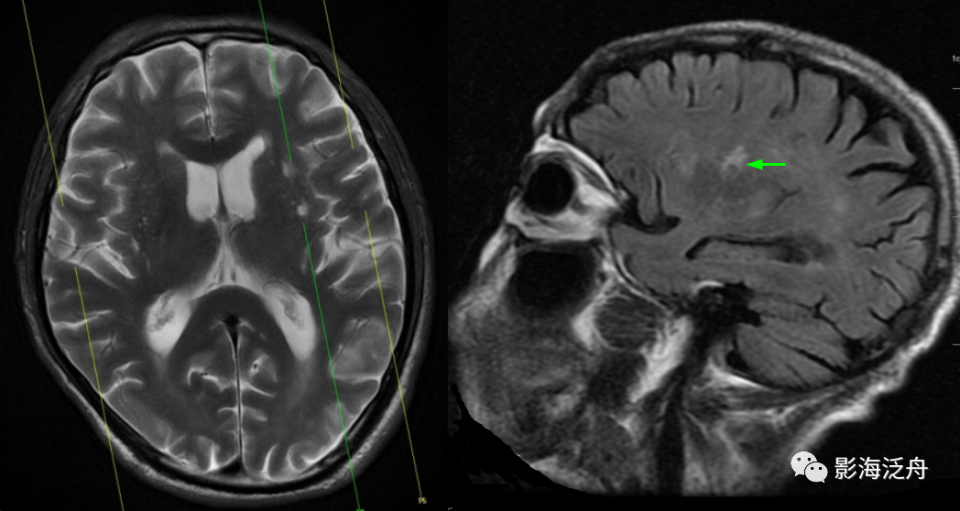

左侧基底节区腔梗灶,病灶既不像类圆形也不像规则的长条状,在Flair序列上灶周可以看到淡淡的高信号影(红箭)。基底节区的腔梗灶位置相较于扩大VR腔隙往往更加靠近上份层面、形态不规则,且随着病程时间延长Flair序列高信号会愈加明显。

图片

左侧基底节区腔梗灶(红箭头),尽管后部的那个病灶看起来有点圆,但在Flair序列病灶周围可以看到非常明显的高信号(绿箭),代表局部胶质增生,证明其为慢性期腔梗灶而非扩大的VR腔隙,其余病变(黄箭)为对称性分布,呈斑点状或长条状,Flair序列灶周无高信号,诊断VR腔隙更为合理。